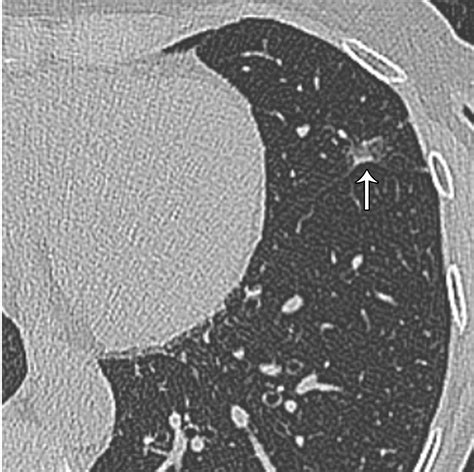

Lung nodules are small, round or oval-shaped growths that appear in the lung tissue. They can be benign or malignant, and their detection often occurs incidentally during imaging studies performed for other reasons. The size and characteristics of these nodules play a significant role in determining the likelihood of malignancy and the need for further evaluation.

The Fleischner Society Criteria classify lung nodules into three main categories based on their size:

• Solid Nodules: These are completely opaque and have a well-defined border.

• Part-Solid Nodules: These have both solid and ground-glass components.

• Ground-Glass Nodules: These are hazy areas of increased lung attenuation without obscuration of the underlying bronchial structures or vessels.